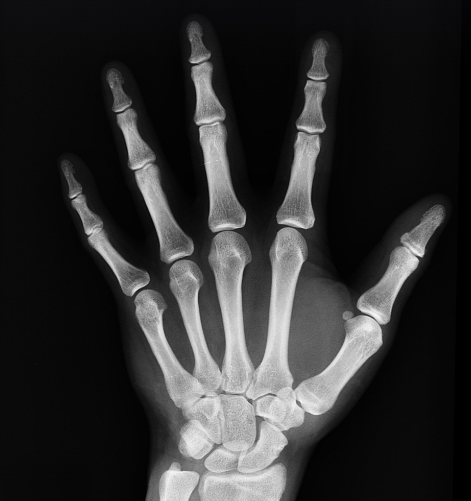

| 쉽게 골절됨 | 손목, 고관절, 척추 부위 골절 위험 증가 |

골다공증이 심해지면 작은 충격에도 쉽게 골절이 발생할 수 있으며, 특히 고관절 골절은 심각한 후유증을 남길 수 있습니다.

노년층에서 고관절 골절이 발생하면 회복이 어려워지고, 활동량 감소로 인해 건강이 급격히 악화될 수 있습니다.